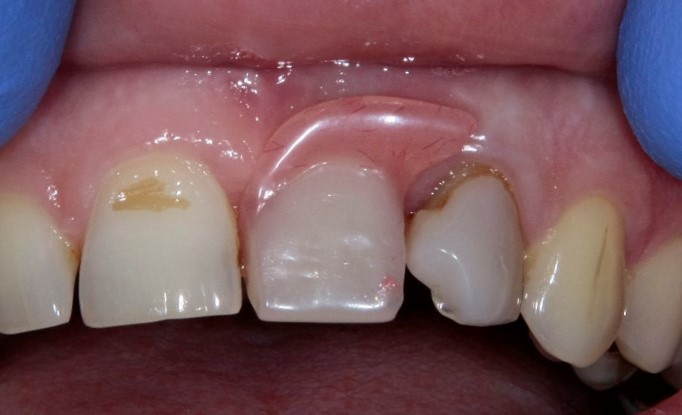

Рекомендации по установке имплантов. Для всех. Часть V.